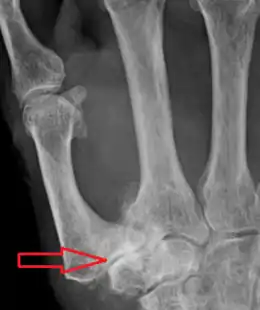

La rhizarthrose se présente sur une radiographie avec des signes classiques d'arthrose : diminution de l'interligne articulaire, ostéophytes (bec de perroquet) marginaux, condensation osseuse sous le cartilage, géode d'hyperpression puis usure osseuse. À ces signes habituels qui définissent l'arthrose vont s'associer dans la majorité des cas une subluxation de la base du premier métacarpien en externe. L'arthrose peut être limitée à l'interligne entre l'os trapèze et le métacarpien ou s'étendre à l'interligne articulaire avec l'os scaphoïde, scapho-trapézo-trapézoïdien (STT), on parle alors dans ce cas d'arthrose péri-trapézienne[4].